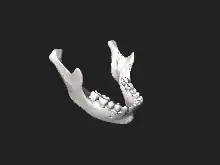

3D model of the mandible